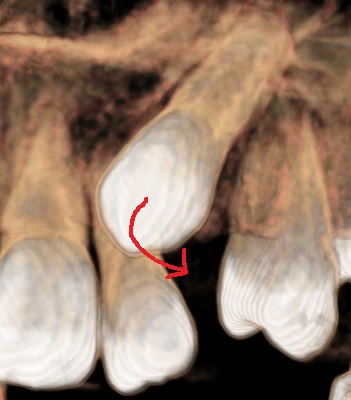

犬歯がでてこない その② 犬歯が他の永久歯の部位にでてきてしまうこともあります。 犬歯が2番目の歯、側切歯を押してしまっているものです。 このままですと側切歯の歯の根が吸収してしまいますので 犬歯の出てくる方向を変えなければなりません。 まずは歯肉をレーザーで切ります。 犬歯にボタンをつけ、引っ張っていきます。 下に引っ張ってきたら全体的に歯を並べていきます。 最近の子は顎が小さいので犬歯が入りきらないことが多いです。 犬歯をかみ合わせにしっかりかみ合わせに参加させて、 将来かみ合わせで苦労しないようにしましょう。 公開日:2016.05.28 矯正歯科 投稿ナビゲーション 前 : 犬歯がでてこない その①次 : 親子受診をはじめよう!